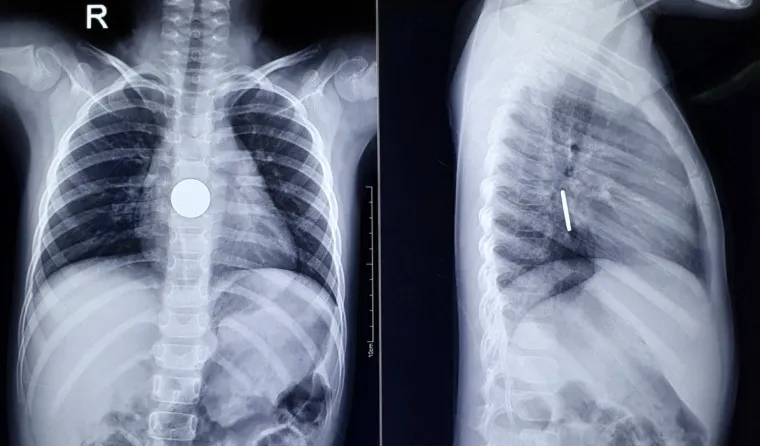

Qua hình ảnh X-quang, dị vật được xác định là đồng xu, đang kẹt ở vị trí cách cung hàm trên 25 - 26 cm, rất gần với dạ dày. Đây là một trường hợp khẩn cấp, nếu không kịp thời gắp dị vật sẽ gây ra tình trạng tắc ruột.